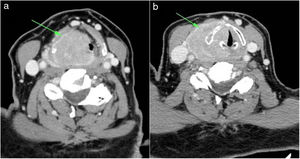

Case reportThe 74-year-old female patient was admitted to the Ear-Nose-Throat (ENT) specialist with complaints of hoarseness and difficulty swallowing that had persisted for approximately 1 year. Her past medical history and physical examination was unremarkable. The direct laryngoscopy revealed a mucosa-covered purple mass lesion arising from the pyriform sinus and lateral pharyngeal wall which nearly obstructed the lumen. Contrast-enhanced CT imaging of the neck revealed a 35×45mm lesion surrounding the right vocal cord and aryepiglottic fold, extending to the supraglottis and the extralaryngeal space with supraglottic airway narrowing (Fig. 1A,B). Size and appearance of the cervical lymph nodes were normal.

Radiological imaging methods are very useful in diagnosis. Also, lesion size, location, invasion of the adjacent tissue, and adjacent bone and cartilage destruction can be evaluated with imaging methods. Calcification and areas with low densities in the thyroid cartilage and infiltrative growth pattern are the typical findings of the EMP, which can seen with CT.10 Also, contrast-enhanced CT usually shows a well-circumscribed homogenous laryngeal mass, which appears with a mild-to-moderate contrast enhancement.1 MRI shows a laryngeal mass with hypointense on T1-weighted images (WIs) and hyperintense on T2 WIs. After injection of intravenous gadolinium, moderate-significant enhancement can be seen in the lesion.4 It is not possible to differentiate definitely EMP of the larynx from other benign and malignant laryngeal tumors by imaging methods. The diagnosis of solitary EMP is based on the exclusion of bone involvement and the demonstration of neoplastic plasma cells by immunohistochemical methods. In addition, in order to make a diagnosis of a solitary EMP there should be no disseminated disease. For this purpose, radiological imaging methods such as X-ray, CT and MRI can be used to evaluate the spine, pelvis, femur and humerus.4,5 Bone marrow biopsy should also be within the normal range. In addition, there should be no signs of serum urine monoclonal protein, anemia, hypercalcemia, or renal impairment.5